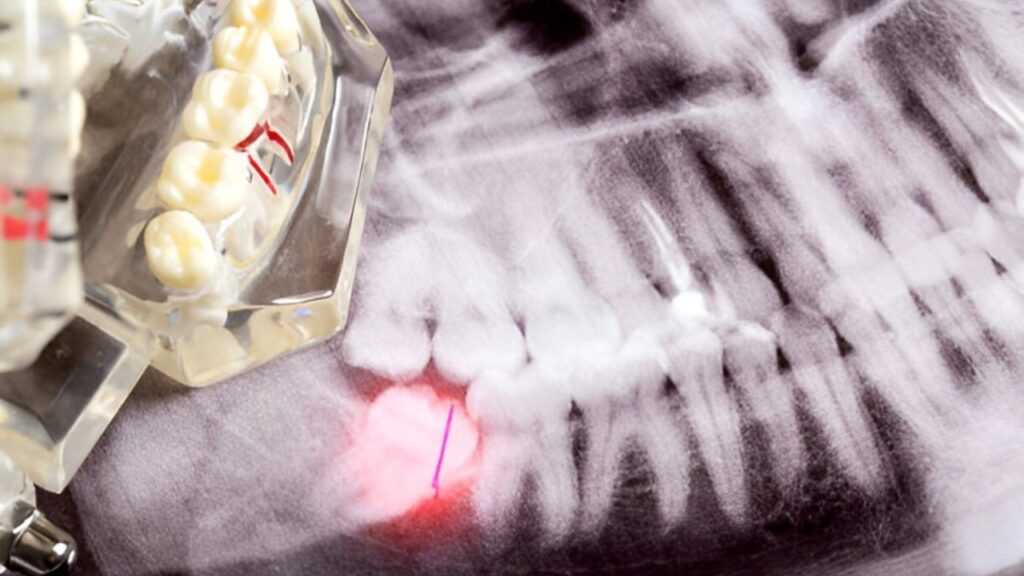

Em casos recorrentes ou graves de pericoronarite, a remoção cirúrgica do tecido gengival sobrejacente ao dente do siso pode ser necessária para proporcionar alívio duradouro e prevenir complicações futuras.

Este procedimento é realizado por um cirurgião oral e pode ser feito com anestesia local ou geral, dependendo da complexidade do caso.